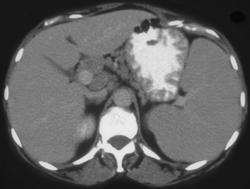

Gastric Ulcer in Adenocarcinoma